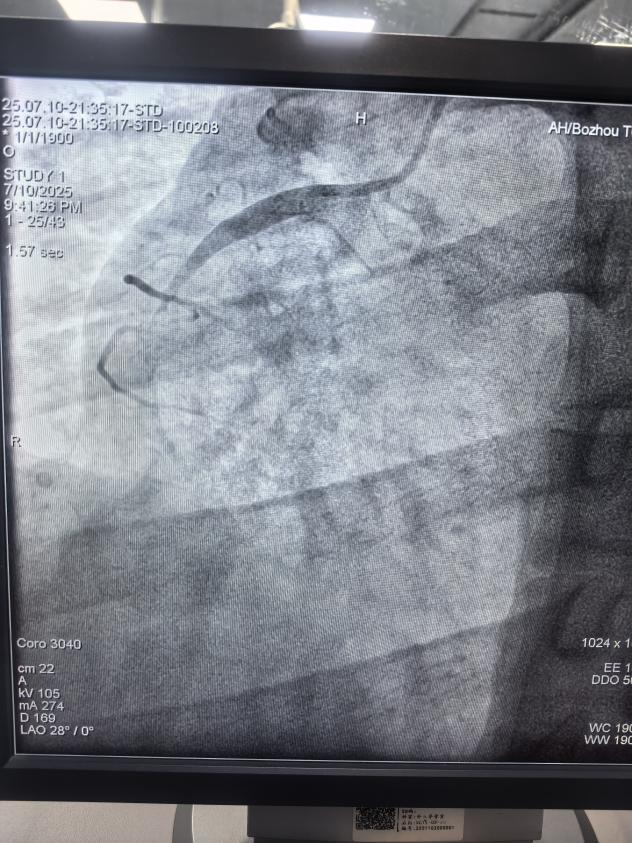

右冠急性閉塞